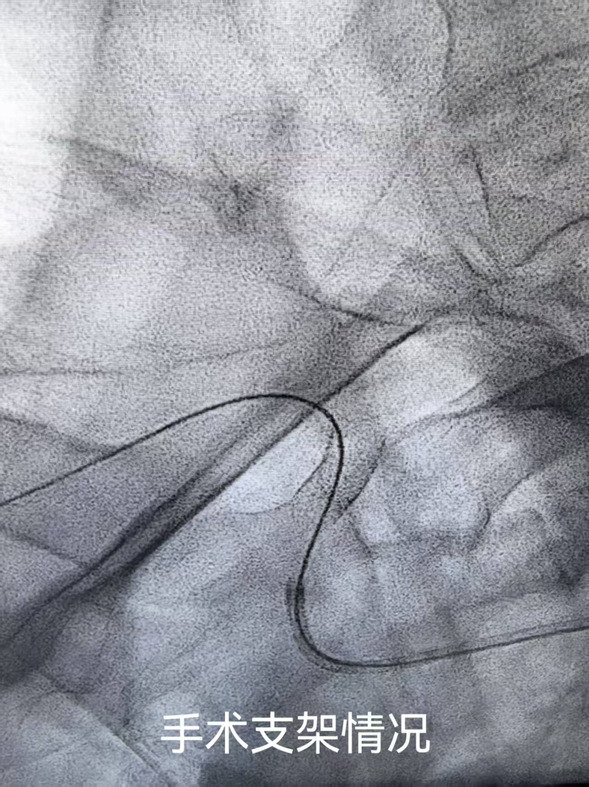

在综合考量患者的身体状况、病情进展及手术耐受程度等多方面因素后,任占军主任带领带领科室医生进行了术前讨论,决定为其实施锁骨下动脉支架置入术,力求消除隐患,让患者重获健康生活。